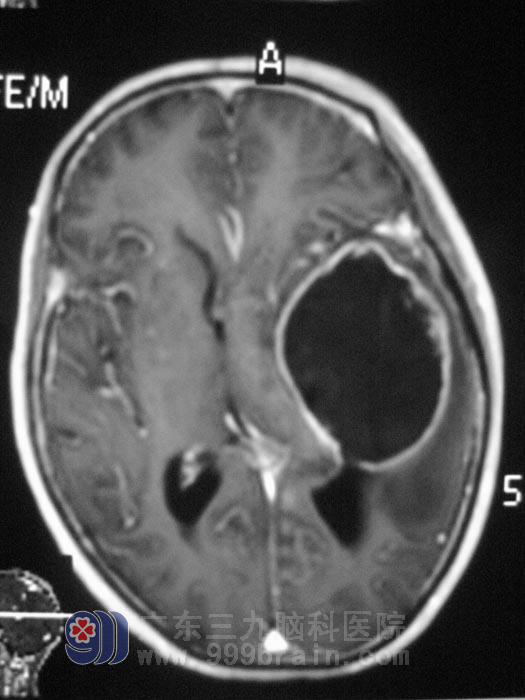

家住汕头的李大爷, 花甲的年龄有着不惑的身体,57岁老人行动、干活不比那些中年人逊色,生活的没有让这位坚强的老人退缩,一周的反复头痛,让老人度日如年。无明显诱因出现反复阵发性头痛,老人的症状谁也没有引起重视,痛起来的时候只是自己吃两片去痛片,症状可以稍减轻,但头痛病再犯的时候,止痛片也不管用了,不但不能干活,还严重影响了李大爷的日常生活,当头痛伴有行走时右侧肢体乏力,偶有头晕,记忆力、反应均较前下降时,家人才意识到不是单纯的头痛了,到医院行颅脑MR检查,结果示:左侧颞叶占位性病变,考虑胶质瘤可能,肿瘤有明显的压迫效应,需要手术切除。http://www.999brain.com/

5月12日,由三九脑科医院神经外五科鲁明主任主刀,在全麻下行左颞叶占位性病变切除术,术中见灰色肿瘤,边界不清,质软,呈烂鱼肉样,在显微镜下予扩大切除,手术后给予抗炎、止血、神经营养等对症治疗,复查MR提示肿瘤全切,老人四肢活动正常,没有出现肢体偏瘫、失语等并发症。术后病理回报:(左颞叶)胶质母细胞瘤,WHOIV级。http://www.999brain.com/

手术前